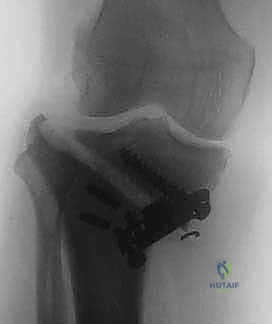

باستخدام أدوات دقيقة ومناشير جراحية متطورة، يتم عمل قطع غير مكتمل في عظمة الساق. هناك طريقتان رئيسيتان:

* الشق المغلق (Closing Wedge): يتم إزالة إسفين (مثلث) صغير من العظم من الجهة الخارجية وإغلاق الفراغ.

4. تعديل المحور:

يتم فتح العظم تدريجياً وببطء شديد حتى الوصول إلى الزاوية التي تم حسابها في التخطيط الرقمي قبل الجراحة.